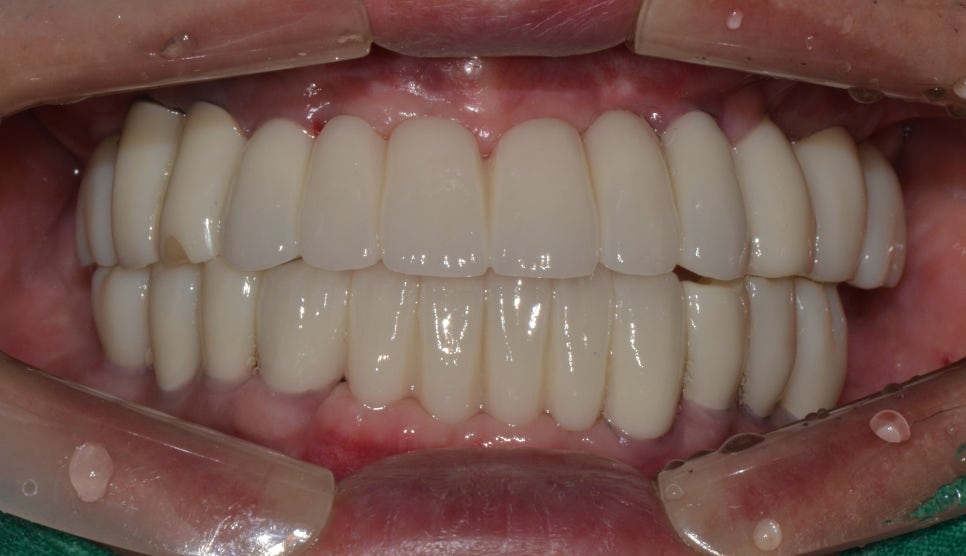

임플란트 치료 후

2022년 4월 1일

치아 위생상태가 좋지 않아 해당 부분도 같이 치료해 주었습니다. 전악 발치를 진행하고 전악 임플란트를 식립해 주어 치료를 마무리해 주었는데요. 중간에 식사를 잘 하실 수 있도록 임시치아도 해드렸습니다. 현재는 많이 구강 상태가 개선이 되어 잘 사용을 하고 계십니다.

명동치과에서 치료 받은 환자분의 전후사례 케이스를 설명드렸는데요. 상실된 치아를 계속해서 내버려 두게 된다면 말씀드린 것처럼 심미성도 떨어지고 저작력도 감소되기 때문에 만약 여러분들의 구강 중 이가 빠진 부분이 있다면 빠르게 치과에 방문하여 검진 받고 본인에게 맞는 방법으로 치료하여 건강한 구강을 가지시길 바랍니다.